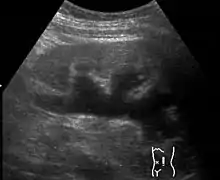

Renal ultrasonography of hydronephrosis caused by a left ureteral stone.

Imaging studies, such as an intravenous urogram (IVU), renal ultrasonography, CT, or MRI, are also important investigations in determining the presence and/ or cause of hydronephrosis. Whilst ultrasound allows for visualisation of the ureters and kidneys (and determine the presence of hydronephrosis and / or hydroureter), an IVU is useful for assessing the anatomical location of the obstruction. Antegrade or retrograde pyelography will show similar findings to an IVU but offer a therapeutic option as well. Real-time ultrasounds and Doppler ultrasound tests in association with vascular resistance testing helps determine how a given obstruction is effecting urinary functionality in hydronephrotic patients.[10]